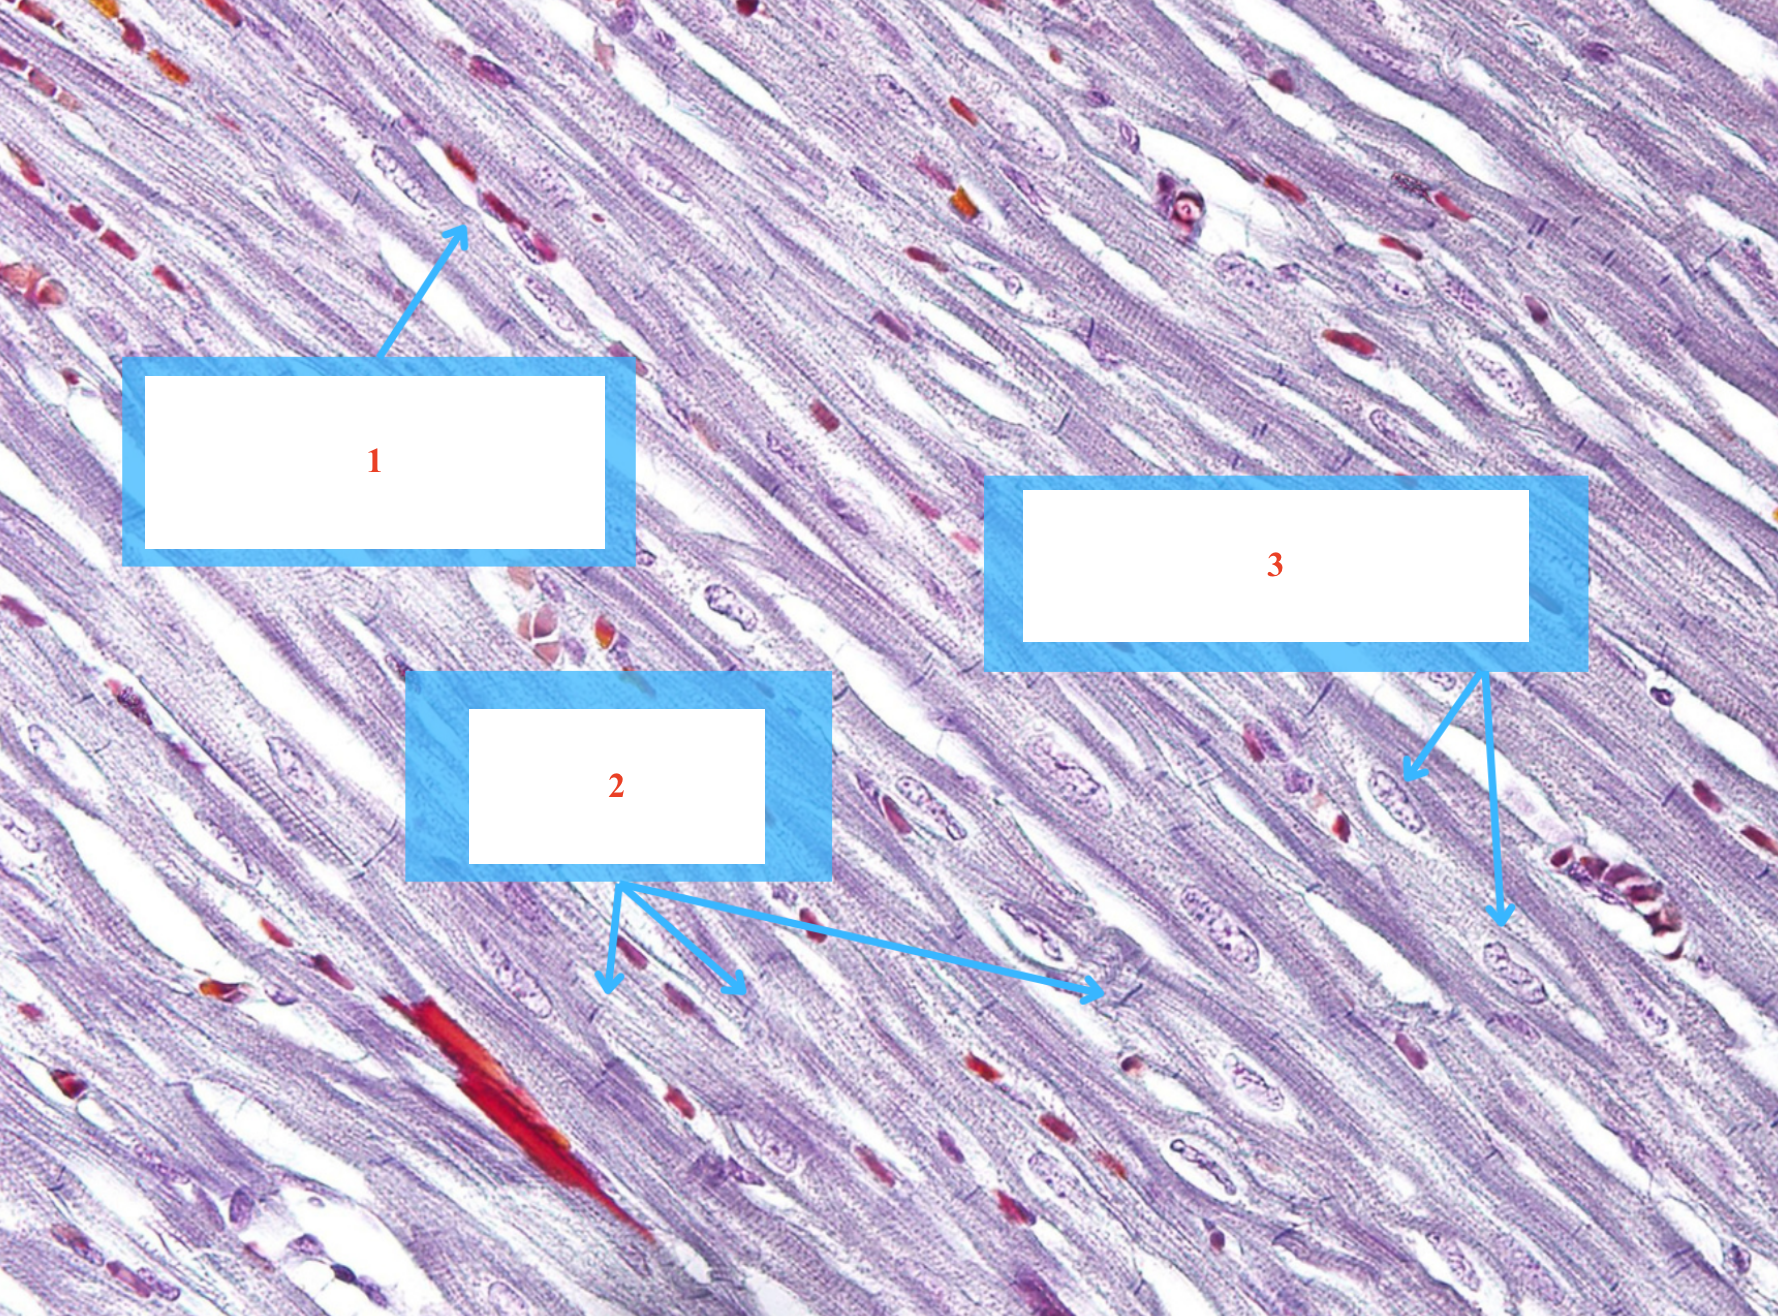

Cấu trúc gì ? (số 1 + 2)

Tế bào gì (số 3)

Khoang Henlé

Đĩa nối

Nhân tế bào cơ tim